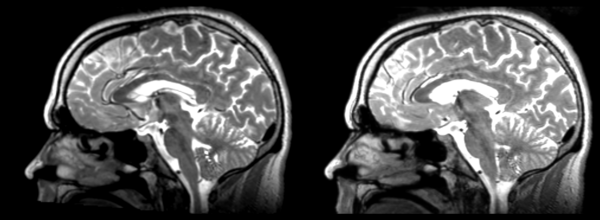

Different subject registration

In this, I'll be moving images like so:

- 01053-t2 -> 01031-t2 = Result. All the images shown have the moving image on the left, the resultant image in the middle, and the target image on the right.

Rigid

01053>01031rigid.png = not bad... different brains of different sizes, but seem to be aligned in the ventricles so output seems okay. output slightly blurry. bad initial leveling displays.

Linear

01053>01031linear.png = not bad... different brains of different sizes, but seem to be aligned in the ventricles so output seems okay.output slightly blurry. bad initial leveling displays.